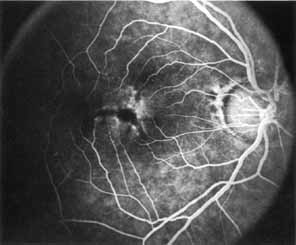

Although there is no reported genetic heterogeneity, there is wide phenotypic variation within the disorder. The major finding within the macula is a classic radial cystic maculopathy. Although retinal signs have been described in infants as young as 3 months, foveal schisis may be difficult to detect, leading to underdiagnosis. The diagnosis is usually not made until the affected male reaches school age (4 to 8 years of age) and encounters visual problems secondary to foveal involvement. Typical foveal schisis findings have been reported in 68% to 100% of eyes within various series.37,38 Foveal schisis is the only finding in about half the cases. It is characterized by the presence of radiate perifoveal microcysts located in the nerve fiber layer (Fig. 1) with radiate plications of the overlying internal limiting membrane that are seen especially well on monochromatic (red-free) photography (Fig. 2). The microcystoid change may slowly progress to form a macular cyst or hole. Foveal schisis has been reported in association with Goldmann-Favre vitreotapetoretinal dystrophy and rarely may be seen in rod-cone dystrophy or as an autosomal dominant or recessive condition.39–43